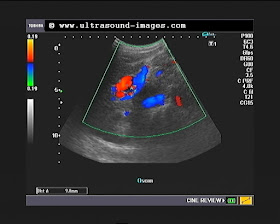

This elderly male patient had generalized discomfort in the abdomen with vague pain in the epigastrium. No h/o alcoholism.